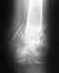

По состоянию на сегодняшний день угол, на который может разгибаться рука, составляет 145 градусов.

Имеет ли смысл дальнейшая разработка руки или может рассмотреть вариант повторной операции.

Всю неделю, пока хожу на разработку руки, рука болит. В выходные немного отпускает.